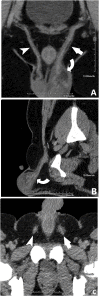

The differential diagnosis of scrotal pain and swelling in adolescent males includes testicular and appendage torsion, epididymitis, epididymo-orchitis, trauma and incarcerated hernia. Physical examination, ultrasound and urinalysis often can identify the etiology of the scrotal pain and swelling. We present a case of left scrotal pain and swelling that was initially concerning for a paratesticular mass. Repeat examination and further imaging during pre-operative assessment was consistent with left-sided vasitis. The diagnosis of vasitis is difficult with ultrasound and commonly requires CT or MRI to differentiate from incarcerated inguinal hernia. Recognition of this uncommonly reported condition may prevent unnecessary surgeries.